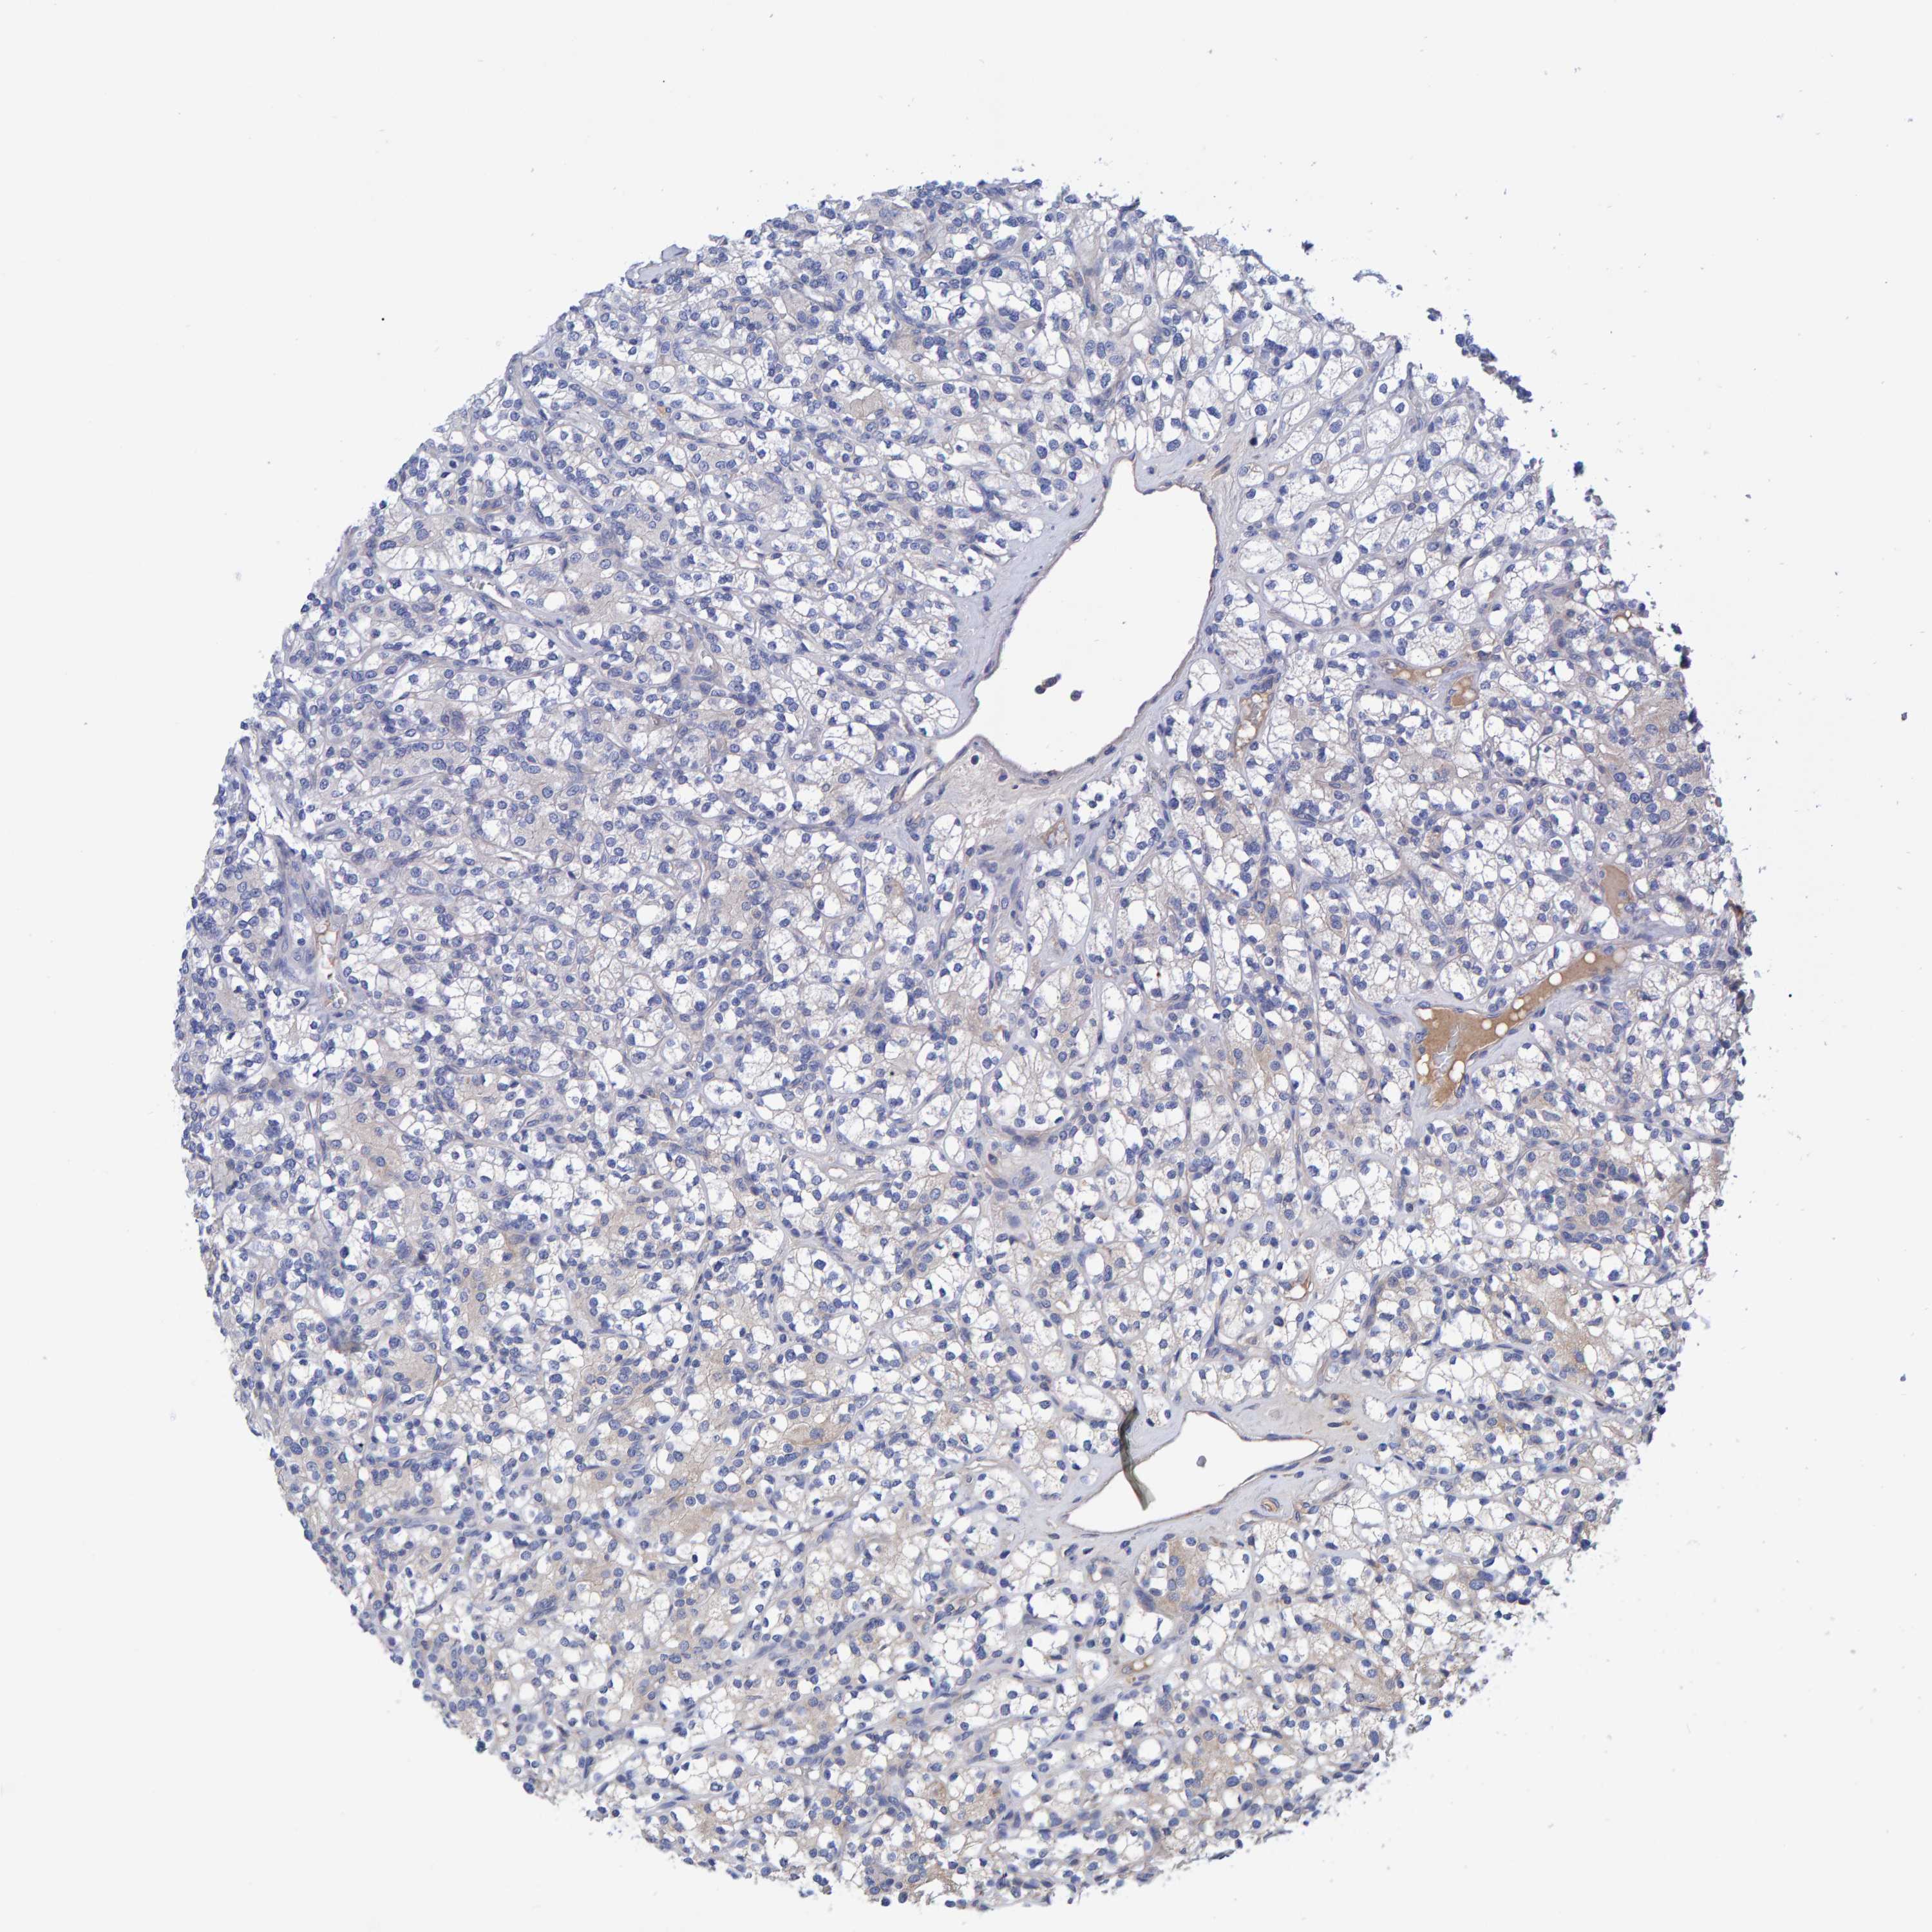

KIDNEY RENAL CLEAR CELL CARCINOMA (VALIDATION) - Interactive survival scatter ploti

The Survival Scatter plot shows the clinical status (i.e. dead or alive) for all individuals in the patient cohort, based on the same data that underlies the corresponding Kaplan-Meier plots. Patients that are alive at last time for follow-up are shown in blue and patients who have died during the study are shown in red.

The x-axis shows the expression levels (FPKM) of the investigated gene in the tumor tissue at the time of diagnosis. The y-axis shows the follow-up time after diagnosis (years). Both axes are complimented with kernel density curves demonstrating the data density over the axes. The top density plot shows the expression levels (FPKM) distribution among dead (red) and alive patients (blue). The right density plot shows the data density of the survived years of dead patients with high and low expression levels respectively, stratified using the cutoff indicated by the vertical dashed line through the Survival Scatter plot. This cutoff is automatically defined based on the FPKM cutoff that minimizes the p-score. The cutoff can be changed by dragging the vertical line or by entering a cutoff value in the square labeled "Current cut-off".

Under the Survival Scatter plot the p-score landscape (black curve; left axis) is shown together with dead median separation (red curve; right axis). Dead median separation is the difference in median mRNA expression between patients who have died with high and low expression, respectively. It is calculated as follows: median FPKM expression of dead patients with high expression - median FPKM expression of dead patients with low expression. This is intended to aid the user in visually exploring custom cutoffs and the associated p-scores and dead median separation.

Individual patient data is displayed and can be filtered by clicking on one or more of the category buttons on the top of the page. Categories describing expression level and patient information include: high, low, alive, dead, female, male and tumor stages. The scale of the x-axis can be toggled between linear and log-scale by clicking on the "x log" button. Mouse-over function shows TCGA ID, patient information and mRNA expression (FPKM) for each patient.

& Survival analysisi

Kaplan-Meier plots summarize results from analysis of correlation between mRNA expression level and patient survival. Patients were divided based on level of expression into one of the two groups "low" (under cut off) or "high" (over cut off). X-axis shows time for survival (years) and y-axis shows the probability of survival, where 1.0 corresponds to 100 percent.

EFR3A is not prognostic in Kidney Renal Clear Cell Carcinoma (validation)

Best expression cut offi

Based on the FPKM value of each gene, patients were classified into two groups and association between prognosis (survival) and gene expression (FPKM) was examined. The best expression cut-off refers the FPKM value that yields maximal difference with regard to survival between the two groups at the lowest log-rank P-value. Best expression cut-off was selected based on survival analysis .

When clicking on this number, the vertical dashed line indicating cut-off, the interactive survival plot, and the Kaplan-Meier curve will be adjusted to show results based on the best expression cut-off.

: 35.91

P scorei

Log-rank P value for Kaplan-Meier plot showing results from analysis of correlation between mRNA expression level and patient survival.

N/A

TCGA RNA samplesi

RNA-seq data is reported as average FPKM (number Fragments Per Kilobase of exon per Million reads), generated by the The Cancer Genome Atlas (TCGA) .

Normal distribution across the dataset is visualized with box plots, shown as median and 25th and 75th percentiles. Points are displayed as outliers if they are above or below 1.5 times the interquartile range. FPKM values of the individual samples are presented next to the box plot.

Average pTPM 35.3

Number of samples 100